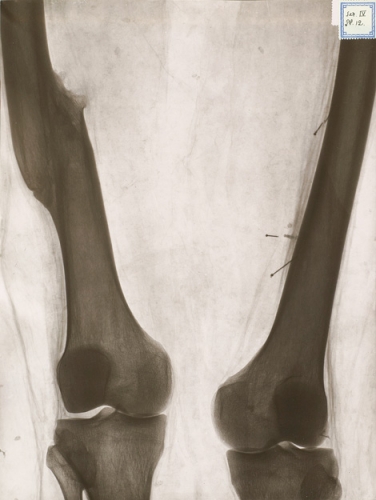

I sitt utlåtande beskriver Gösta Forsell bland annat en snedfraktur ungefär mitt på kungens vänstra lårben. Brottytan mäter 8 cm och är utan vinkelfelställning fastläkt med en tät kallusbildning med ett nybildat system av benbalkar. Förkortningen uppskattas till 3 cm. Karl XII:s kroppsmått mättes med millimeternoggrannhet och hans kroppslängd beräknas till 179 cm. Det högra benet från höftbenskammen till fotsulan var 1 100 mm och det vänstra 1 063 mm. Vidare konstaterar Forsell att »det finns en läkt skada vid basen av femte metatarsalbenet, läkta frakturer genom diafyserna på fjärde och andra metatarsalia samt defektläkt fraktur genom tredje metatarsen där den distala hälften av benet saknas. Man ser även en hel del kvarvarande metallfragment. Det finns vidare rikligt med benpålagringar på mellanfotsbenen, vilka tolkas som spår av kronisk infektion, både i benvävnaden som osteit och i angränsande mjukdelar.« (Den borttagna distala hälften av det tredje metatarsalbenet återfanns för övrigt i en sidenpåse i graven.)